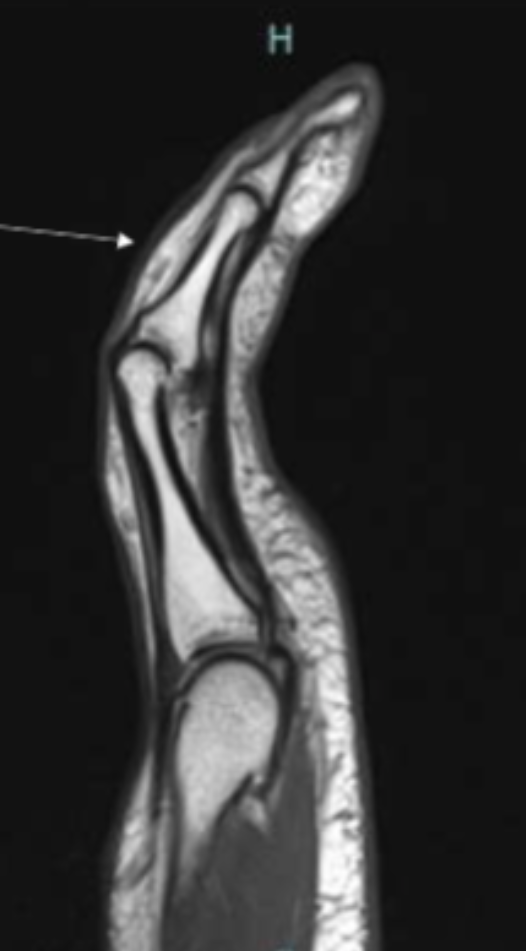

Describe the pathology indicated by the arrow (Sag PD).

Extensor tendon tear